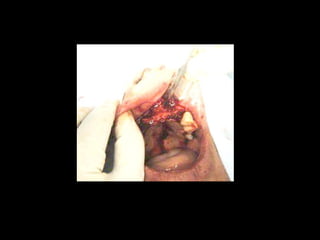

Trismus importante debidoa queTrismus importante debido a que El tumor ya rompió el hueso com-El tumor ya rompió el hueso com- Pacto de la cara interna de laPacto de la cara interna de la Mandíbula y empezó a tomar elMandíbula y empezó a tomar el Músculo pterigoideo interno.Músculo pterigoideo interno.

Area de lisisósea a nivel de la líneaArea de lisis ósea a nivel de la línea Miliodes que contracturó los músculosMiliodes que contracturó los músculos Milohioideo y pterigoideo internoMilohioideo y pterigoideo interno Dificultando la deglución y determinandoDificultando la deglución y determinando Trismus importante.Trismus importante. Pieza en proceso de examen por histopatologíaPieza en proceso de examen por histopatología